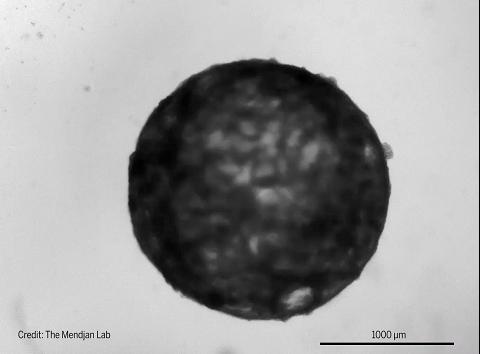

图 | 跳动的心脏类器官(来源:The Mendjan Lab)